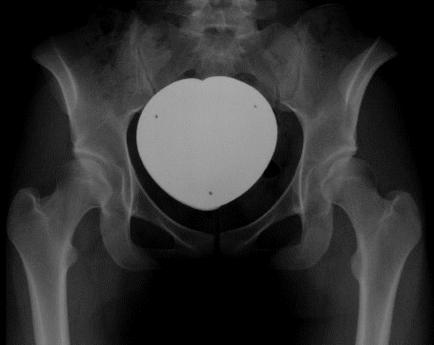

In residual hip dysplasia periacetabular osteotomy (PAO) can improve insufficient coverage of the femoral head. It requires a broad dissection of the pelvic bones and detachment of muscle insertions, however. We have developed a modification of the Bernese periacetabular osteotomy with reduced soft tissue exposure. It uses two small skin incisions and offers therefore the perspective of nicer scars but also increases the risk of technical complications due to impaired vision. To be able to draft these risks, the clinical and radiographic results of 23 patients with PAO through the modified Smith-Petersen approach of Ganz (group A) and 24 patients with our two-incision modification (group B) have been reviewed retrospectively with an average follow-up of 19 (group A) and 12 (group B) months postoperatively.Functional improvement (Harris Hip Score) and center-edge-angle normalization did not differ significantly in both groups. Scars of patients in group B were significantly shorter. However, the overall patient satisfaction (as measured with a visual analogous scale) was the same in both groups. 4 patients in group A and one patient in group B developed superficial or deep wound infections.In conclusion, the experience with our cohort study showed that approach-related morbidity can be reduced without increasing the risk for the individual patient. This observation clearly holds a promise for further minimal invasive approaches as well as for further morbidity reduction of PAO.

在残留性髋关节发育不良中,髋臼周围截骨术(PAO)可改善股骨头覆盖不足的情况。然而,该手术需要广泛剥离骨盆骨并切断肌肉附着点。我们对伯尔尼髋臼周围截骨术进行了改良,减少了软组织暴露。该改良术式采用两个小切口,因此有望形成更美观的瘢痕,但由于视野受限也增加了技术并发症的风险。为了评估这些风险,我们回顾性分析了23例采用改良甘茨史密斯-彼得森入路行PAO手术的患者(A组)和24例采用我们的双切口改良术式的患者(B组)的临床及影像学结果,术后平均随访时间分别为19个月(A组)和12个月(B组)。两组患者的功能改善情况(Harris髋关节评分)和中心边缘角正常化情况无显著差异。B组患者的瘢痕明显更短。然而,两组患者的总体满意度(采用视觉模拟量表测量)相同。A组有4例患者和B组有1例患者发生了浅表或深部伤口感染。总之,我们的队列研究经验表明,在不增加个体患者风险的情况下,可以降低手术相关的发病率。这一观察结果显然为进一步的微创方法以及降低PAO的发病率带来了希望。